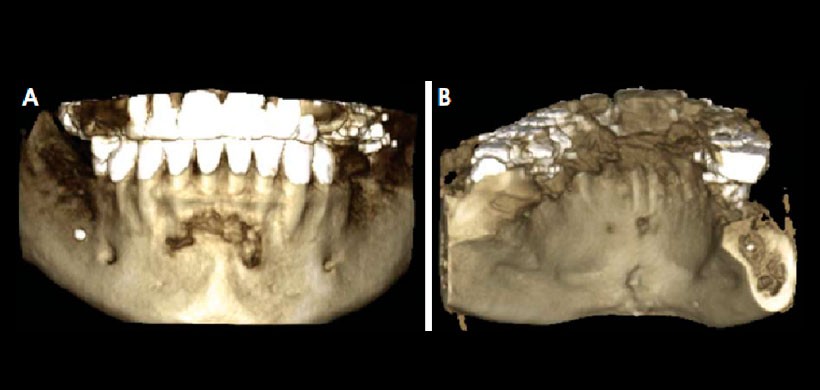

Fig 3. Reconstrucción 3D de la tomografía volumétrica. A. La vista frontal muestra la erosión de la cortical bucal de la lesión. B. La vista lingual muestra que la lesión erosiona la cortical lingual.